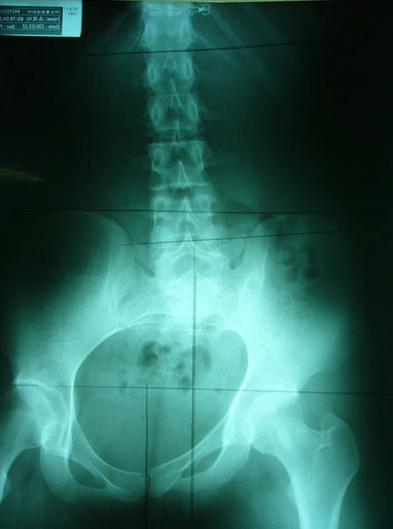

理想骨盆相对位置:两边骨盆、股骨头对称等高、中线穿过腰椎荐椎与耻骨联合、骨盆环呈现对称心形

严重不对称案例,伴随腰椎向左倾斜